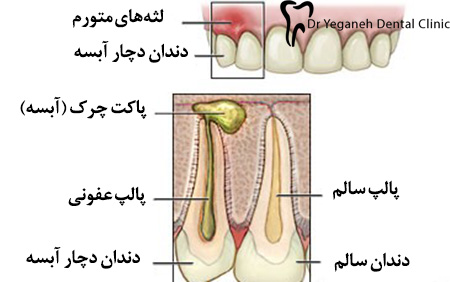

دلیل عفونت دندان و لثه رشد مستقیم باکتری از فضاهای پالپ یک دندان یا سطوح عمیق ریشه یک دندان به بافتهای نرم و استخوانهای نگهدارندهی صورت و گردن است.از عواملی که ابتلا به عفونت لثه و دندان را زیاد می کند می توان به بیماری های دیابت و خشکی دهان و … اشاره کرد.

دو نوع آبسه وجود دارد: آبسه لثه یا آبسه دندان.

آبسه دندان (آبسه پریاپیکال)

آبسه دندان در داخل دندان رخ میدهد. این وضعیت زمانی پدید میآید که عصب دندان مرده باشد یا در حال از بین رفتن باشد. این نوع آبسه در نوک ریشهی دندان آغاز شده و سپس به استخوان اطراف گسترش پیدا میکند.